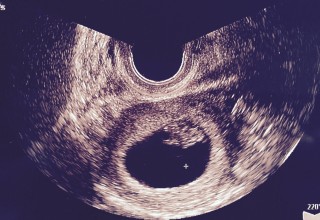

自分で数えて8w目頃。検査薬もわざと生理予定日から20日くらい我慢して(笑)2回とも陽性!!!!!(2016/2/15)昨日!!!初診行ってきました!!!!1人目BABYです!1発で心拍を確認したくてちょっと遅めに行ったら実際は7w5dでちょっとズレてましたが、12mmの二頭身!!無事確認できました!胸の張りや食べつわりっぽいのはありましたが、全然軽くて他のつわりもなかったので、長めに待って診察に行きました!つわりがきつい人はオススメしませんが汗心臓がすごいスピードで動いてて、エコー写真もらっ時はやっぱり感動するんですね(笑)このサイトはよく見てたので、皆さんからコウノトリ頂けたので♪私も送ります!